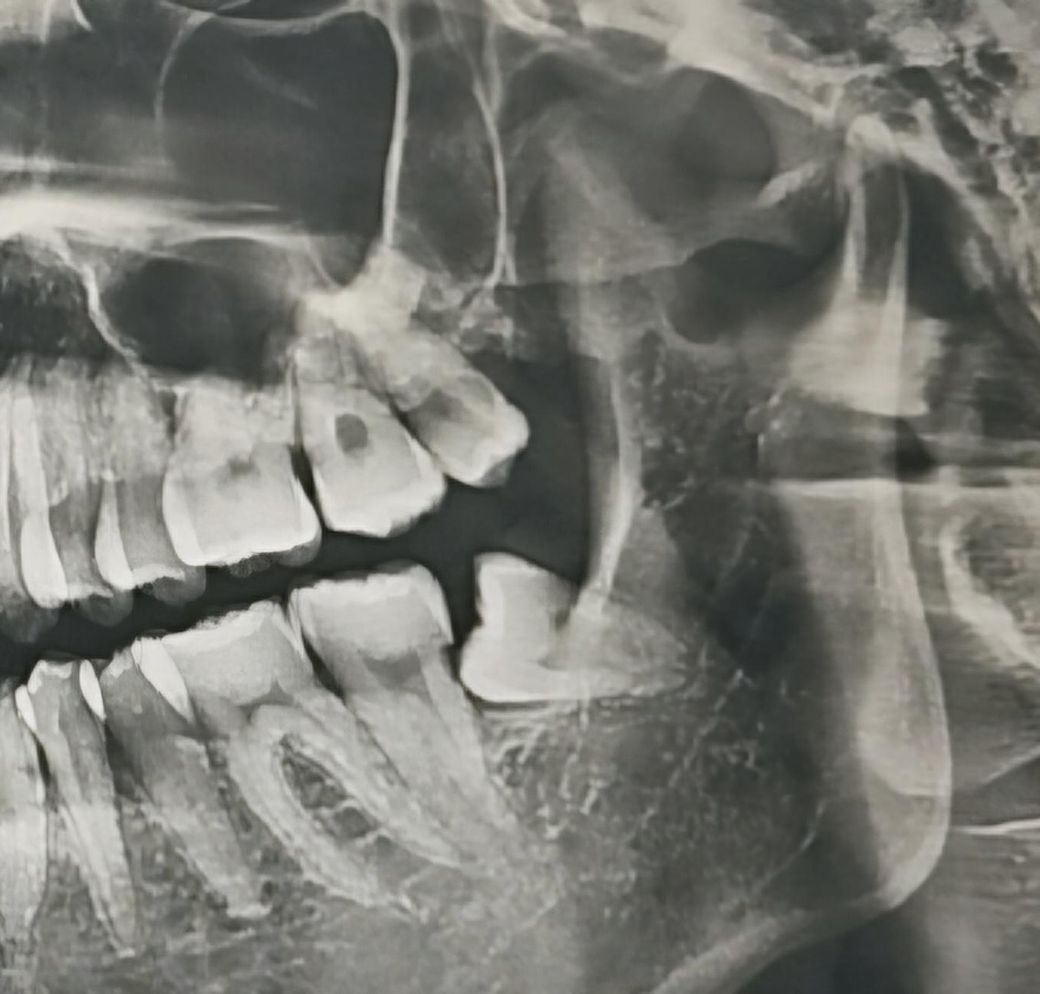

이번 주 월요일(11월4일)에

좌측 하악 매복사랑니를 발치하여 봉합을 하였고

판단하시는데 조금이라도 도움이 되실까 싶어

발치 전 CT촬영 사진도 함께 첨부하겠습니다.